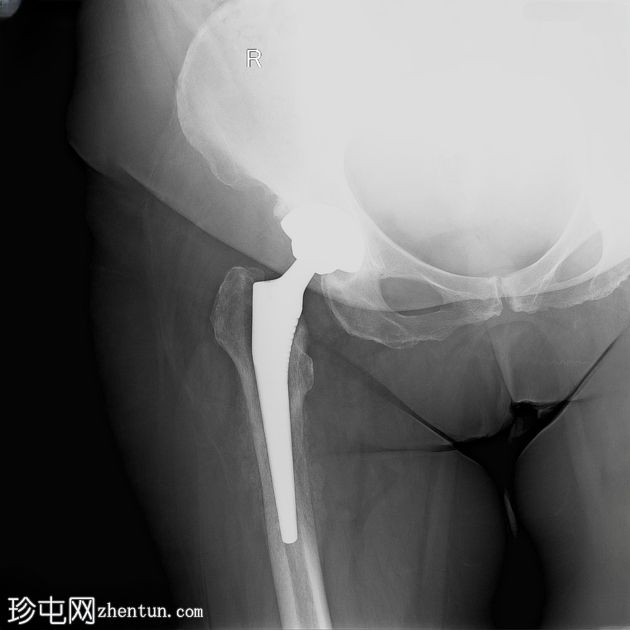

3.jpeg

侧面

右侧股骨骨干近端1/3可见明显的骨皮质变形,并伴有环状骨膜反应。内侧和腹侧表面可见边界清晰的椭圆形透亮区,最大直径约1厘米和2厘米,为骨皮质渗透区。

在本例中,尽管最初使用抗生素治疗后感染似乎得到缓解,但患者仍出现持续性局部疼痛和慢性骨受累的放射学征象,包括骨膜反应和可能的松动。

这些发现提示慢性骨髓炎,这是一种细菌在骨内持续感染的疾病,通常由于假体等异物的存在和细菌生物膜的形成而加剧。影像学检查中出现的透亮病灶进一步支持了诊断,反映了持续感染导致的骨皮质浸润。